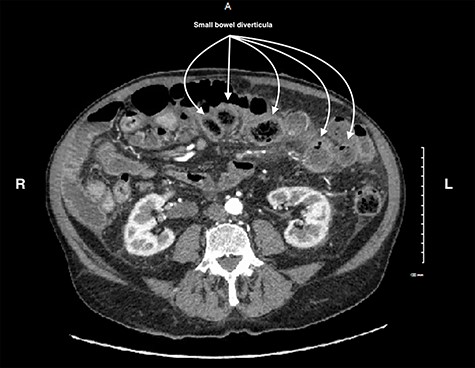

A 79-year-old male presented with 2 weeks of persistent abdominal pain. He did not report any nausea, vomiting or chills. Past medical history included aortic stenosis and type II diabetes, and no history of previous abdominal surgery. His abdomen was soft, non-distended, with mild generalized tenderness and an incidental umbilical hernia. Vitals signs were normal. His white blood cell count was 16.7 × 109/L. CT identified multiple distended and inflamed jejunoileal diverticula. There was no free fluid or gas (Fig. 1). The patient was admitted with small bowel diverticulitis and managed with bowel rest and intravenous antibiotics. He was discharged on post-admission Day 3.

CT scan of the abdomen and pelvis showing small bowel diverticula with inflammation and stranding consistent with uncomplicated diverticulitis.